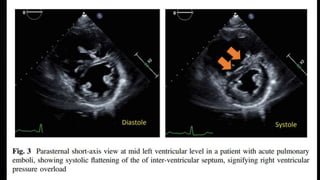

ECHOCARDIOGRAPHY IN PE

• Manifestations of RV pressure overload and dysfunction

• RV dilatation seen in >25% of patients with PE on TTE and is useful for risk stratification

of the disease

• 60/60 Sign : combination of a pulmonary ejection acceleration time (measured in the RV

outflow tract) of <60ms AND a peak systolic tricuspid valve gradient of <60mmHg

• McConnell’s sign : depressed contractility of the RV free wall when compared to the RV

apex

• Finding present only in 12-20% of unselected PE patients

• Decreased tricuspid annular systolic plane excursion (TAPSE) may also be seen in PE

• Mobile right heart thrombi (in up to 18% of PE in the ICU) essentially confirm the

diagnosis of PE and associated with high mortality rates

• Echo is not mandatory as a part of workup in hemodynamically stable patients with PE

• BUT in suspected high-risk PE, absence of echocardiographic signs of RV overload

practically excludes PE as the cause of hemodynamic instability. Can give a pointer

towards the differential diagnosis of the actual cause of shock

• Conversely, in a hemodynamically compromised patient with suspected PE, unequivocal

signs of RV pressure overload such as the McConnell’s sign or the 60/60 sign justify

emergency reperfusion treatment for PE if immediate CTPA is not feasible in a patient

with high clinical probability and no other obvious causes for RV pressure overload.

ECHOCARDIOGRAPHY IN PE •Manifestations of RV pressure overload and dysfunction • RV dilatation seen in >25% of patients with PE on TTE and is useful for risk stratification of the disease • 60/60 Sign : combination of a pulmonary ejection acceleration time (measured in the RV outflow tract) of <60ms AND a peak systolic tricuspid valve gradient of <60mmHg • McConnell’s sign : depressed contractility of the RV free wall when compared to the RV apex • Finding present only in 12-20% of unselected PE patients • Decreased tricuspid annular systolic plane excursion (TAPSE) may also be seen in PE • Mobile right heart thrombi (in up to 18% of PE in the ICU) essentially confirm the diagnosis of PE and associated with high mortality rates

• Echo isnot mandatory as a part of workup in hemodynamically stable patients with PE • BUT in suspected high-risk PE, absence of echocardiographic signs of RV overload practically excludes PE as the cause of hemodynamic instability. Can give a pointer towards the differential diagnosis of the actual cause of shock • Conversely, in a hemodynamically compromised patient with suspected PE, unequivocal signs of RV pressure overload such as the McConnell’s sign or the 60/60 sign justify emergency reperfusion treatment for PE if immediate CTPA is not feasible in a patient with high clinical probability and no other obvious causes for RV pressure overload.